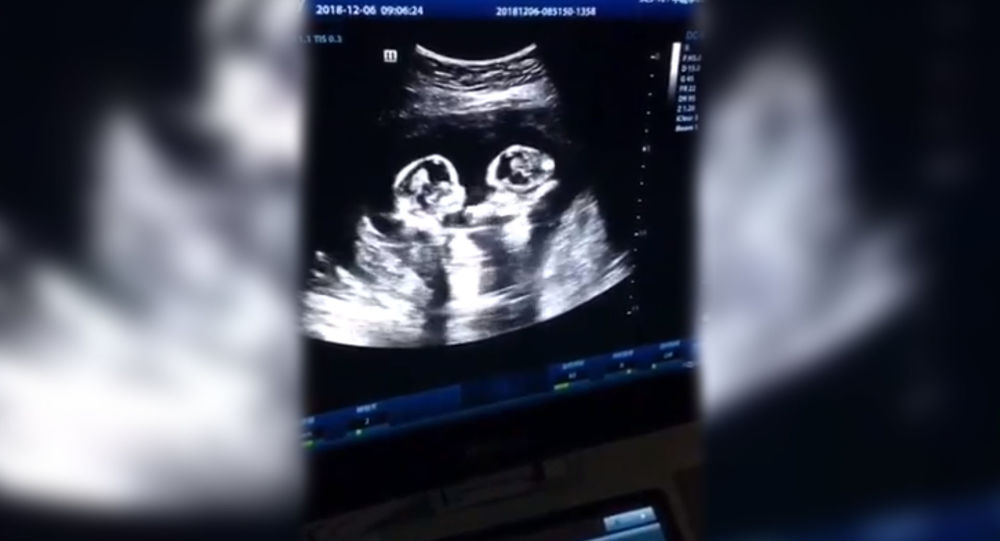

Сестры-близнецы "подрались" в утробе матери прямо во время сонографии

Сестры-близнецы \“подрались\» в утробе матери прямо во время сонографии Ультразвуковое исследование (УЗИ) показало родителям в Китае общение их еще нерожденных детей в утробе матери на четвертом месяце беременности, сообщает Daily Mail. Видео ультразвука удалось записать отцу сестер-близняшек.

По кадрам ролика кажется, будто девочки дерутся в животе у матери. Это зрелище так позабавило их 28-летнего отца, что он поделился видеозаписью сонограммы в Сети. Ролик быстро распространился среди пользователей интернета и набрал более 2,5 миллионов лайков и 80 тысяч комментариев.

Близнецы делили один амниотический мешок и плаценту в утробе матери. Такое явление встречается редко и является одной из самых рискованных форм беременности — только 50 процентов детей в таком случае выживает. Отмечается, что героини ролика уже родились абсолютно здоровыми путем кесарева сечения.